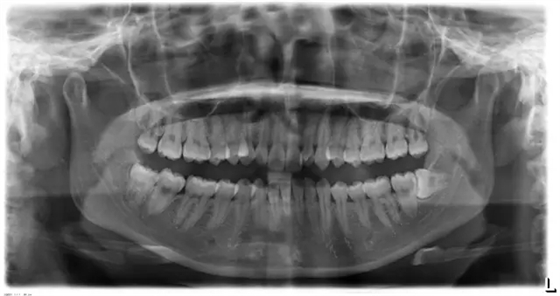

上下牙列擁擠,磨牙尖牙Ⅱ 類關(guān)系,3 度的深覆牙合,上頜中切牙伸長內(nèi)傾拔除上頜雙側(cè)的第一前磨牙,先粘上頜高轉(zhuǎn)矩的自鎖托槽排齊牙列,唇向開展上頜切牙,有一定的覆蓋,粘下頜標準轉(zhuǎn)矩托槽,上頜 1, 2 之間植入種植支抗壓入,同時后牙 5, 6 之間植入種植支抗內(nèi)收前牙,打開咬合關(guān)閉間隙。治療關(guān)鍵:前牙轉(zhuǎn)矩的控制第 1 個月 上頜粘上 Damon Q 高轉(zhuǎn)矩托槽,上 .014 熱激活 NiTi 絲。第 3 個月 上換 .014 x .025 熱激活 NiTi 絲。第 5 個月 上頜基本排齊,覆蓋增大,上換 .017 x .025 NiTi絲,下頜粘托槽,下 .014 熱激活 NiTi 絲。第 7 個月 上 .017 x .025 NiTi 絲加搖椅,下?lián)Q .014 x .025 熱激活 NiTi 絲第 9 個月 上頜換 .019 x .025 NiTi 絲加搖椅,下頜換 .017 x .025 NiTi 絲第 11 個月 下頜換 .019 x .025 加搖椅,上頜 1, 2 之間, 5, 6 之間植入種植釘,下頜出現(xiàn)散隙。第 13 個月 上頜換 .019 x .025ss 加搖椅,前牙種植釘用 Power Chain 壓低前牙(每側(cè) 100g),后牙種植釘關(guān)閉間隙(每側(cè) 150g),下?lián)Q .019 x .025ss,Power Chain 關(guān)閉間隙。第 19 個月 上頜前牙基本壓低到位去除前牙種植釘,繼續(xù)用關(guān)閉間隙,下頜散隙關(guān)閉。

第 22 個月 上頜覆蓋變小,去除 5, 6 之間種植釘,后牙前移關(guān)閉間隙。第 30 個月 患者未配合中線牽引,下中線仍有 1mm 右偏,患者對矯治效果滿意要求拆除,拆除固定矯治器,取模制作壓模保持器。 1.骨性 Ⅱ 類的患者內(nèi)收前牙時需對上頜前牙的轉(zhuǎn)矩進行較好的控制才能獲得良好的面型和唇部形態(tài)。 2.露齦笑的患者治療前要分析其病因是唇、牙齦、牙齒、牙槽骨、上頜骨或多種因素結(jié)合,再制定矯治方案。 3.Ⅱ 類第二分類伴露齦笑的患者的上頜前牙移動軌跡是唇向開展-壓低-整體內(nèi)收。 4.Ⅱ 類第二分類牙齒舌傾比較厲害的情況,上頜中切牙慎用樹脂咬合墊。 5.壓低前牙或控根移動時容易發(fā)生牙根的吸收,需輕力緩慢的移動。